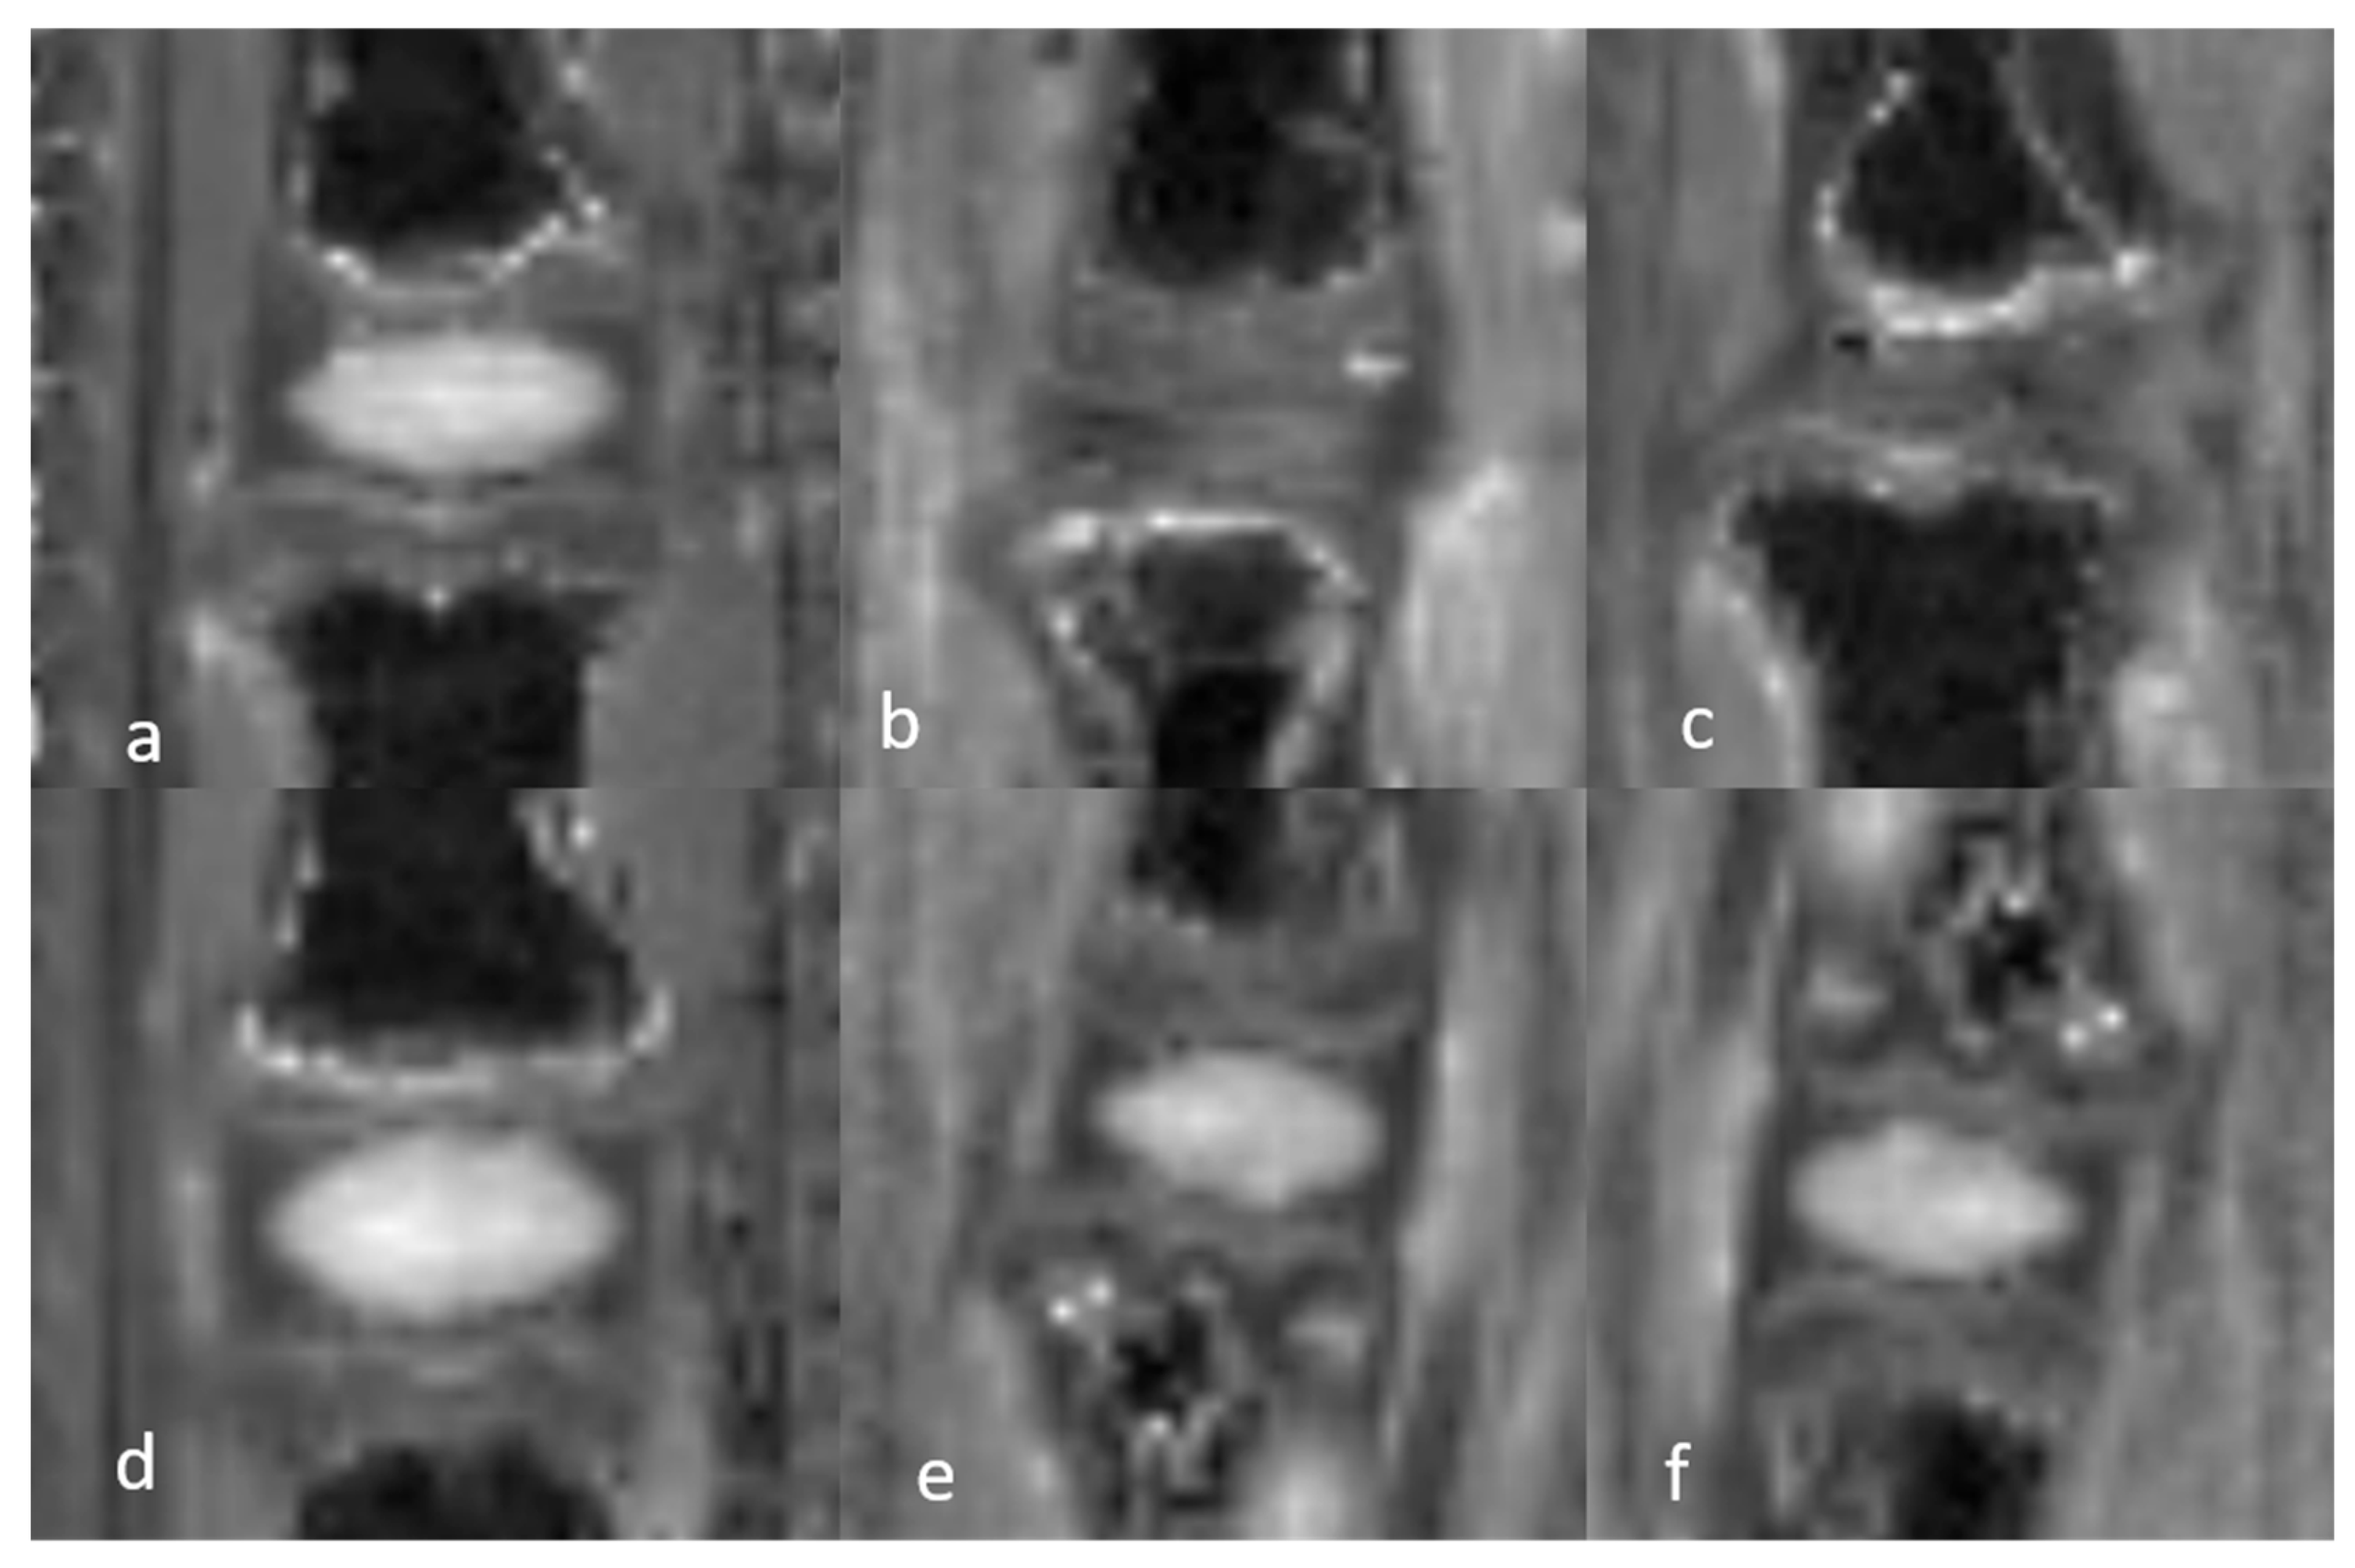

3.1. Image Analysis

3.1.2. Qualitative Analysis of the DVC in DDD Rats (Table 3)

3.1.3. Quantitative Analysis of the Normal DVC (Table 4)

3.1.4. Quantitative Analysis of the DVC in DDD Rats (Table 4)